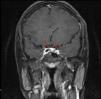

A 24 year old primi mother who underwent lower segment caesarean section (LSCS) at 39 weeks’ gestation due to maternal request and small for gestational age in February 2024, presented to the emergency department with complaints of headache, blurring of vision, polydipsia, and polyuria on the fourth postoperative day. She had no features of pre-eclampsia and she had normal lab parameters during her entire antenatal period. Her baby weighed 2400g and the placenta weighed approximately 400g. On examination, she had a blood pressure of 180/100mm Hg without any focal neurological deficits. She was administered labetalol and intravenous magnesium (4g bolus followed by 2g/h infusion) according to the gynaecological protocol for eclampsia. Her antihypertensives included oral sustained release nifedipine and labetalol. Fundoscopy revealed a normal fundus. Lab revealed serum sodium – 144meq/l, potassium – 3.7meq/l, creatinine – 0.6mg/dl, blood urea nitrogen – 7.4mg/dl, glucose – 124mg/dl, haemoglobin – 11.6g/dl, WBC – 7600/mm3, platelets – 258,000/mm3, glucose – 124mg/dl, bilirubin – 1.1mg/dl, SGOT – 52IU/l and SGPT – 48IU/l. Urine examination revealed sterile urine with a specific gravity of 1005 and proteinuria of 190mg/day without active urinary sediments. The calculated serum osmolality was 298mOsm/kg, urine osmolality – 87.8mmol/kg and she had a urine output of 300–400ml/h. Due to low specific gravity, low urine osmolality, elevated serum sodium levels, and polyuria, she was diagnosed with diabetes insipidus and started on 10μg nasal puff in each nostril twice a day (cumulative dose: 40μg/day). Two hours after the desmopressin nasal puff, her urine osmolality increased to 305mmol/kg and her urine output gradually decreased to 100–150ml/h. Her urine output was 5700ml/day on the first day of admission. She was managed with different intravenous fluids (0.45% normal saline and Ringer's lactate) as per the serial electrolyte levels (Table 1) to ensure euvolemia. Her urine volume gradually decreased to 2.3l on Day 4. Withdrawal of nasal DDAVP on Day 5 of admission resulted again in polyuria with repeat urine osmolality – 104mOsm/kg thereby confirming the diagnosis of central diabetes insipidus. MRI of the pituitary gland revealed a normally sized pituitary midline pituitary stalk with differentially enhanced foci measuring 6mm×4mm and 5mm×4mm in the right and left lateral aspects, respectively (Fig. 1). Abdominal ultrasonography revealed a normal postpartum uterus. Her 8 am serum cortisol level was 11mcg/dl, serum TSH was 2.45mIU/l and serum prolactin level was 246mU/l indicative of an intact anterior pituitary hormonal axis. Her serum ADH was found to be less than 1pg/ml. Her antihypertensives were weaned off to one antihypertensive medication upon discharge. She was transitioned to oral DDAVP (0.1mg thrice a day) on Day 6 and discharged with complete resolution of polyuria and polydipsia. She has stable electrolytes without polyuria on review with complete tapering of DDAVP within 3 weeks. Repeat serum ADH levels was found to be 2.3pg/ml after stopping DDAVP on review after 1 month.